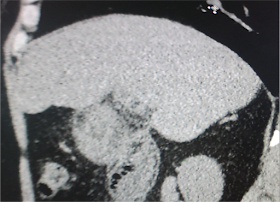

MDCT OF ABDOMEN WITH CE SHOWED ODDI AMPULA HAVING A MASS WITH CE (SEE 2 CT IMAGES).